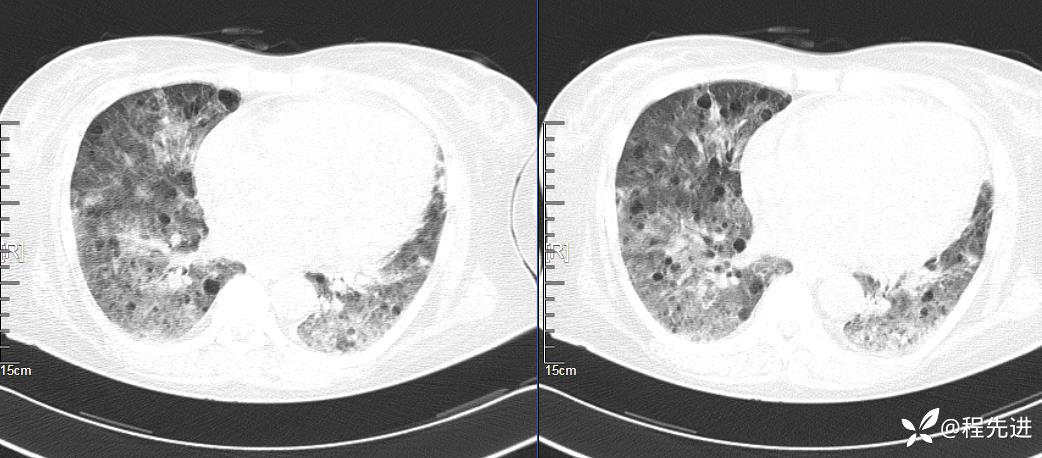

简要病史:胸闷、气促、进行性呼吸困难5年,双下肢浮肿、恶心呕吐1周

CT平扫(纵隔窗无特殊,就不上传了):

1、两肺弥漫性肺气囊的鉴别诊断有哪些?

2、本例肺气囊分布有什么特点?肺气囊有无小叶核心?有没有间质纤维化及伴发结节?